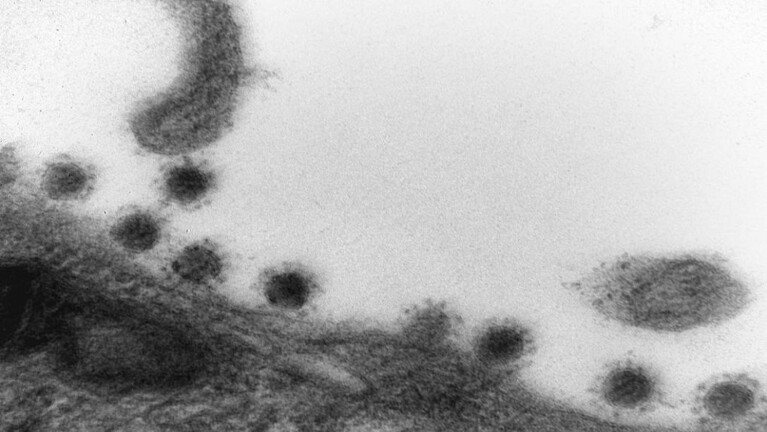

مدير منظمة الصحة العالمية يعلن وقت انتهاء كورونا..وإعلان مزعوم عن دولة لم يدخلها الوباء

قال المدير العام لمنظمة الصحة العالمية (WHO) تيدروس أدهانوم جيبريسوس ، إن فيروس كورونا سينتهي عندما تبدأ جميع البلدان في استخدام الأدوات الصحية المتاحة بشكل فعال، وفق ما ذكر موقع وين.

ذكر جيبريسوس “سينتهي الوباء عندما يختار العالم إنهاءه إنه في أيدينا. لدينا جميع الأدوات التي نحتاجها: أدوات الصحة العامة الفعالة والأدوات الطبية الفعالة. لكن العالم لم يستخدم هذه الأدوات بشكل جيد”.

وأضاف تيدروس ، في خطابه أمام قمة الصحة العالمية في برلين ، إن الوباء لم ينته بعد مع ما يقرب من 50 ألف حالة وفاة أسبوعيا.